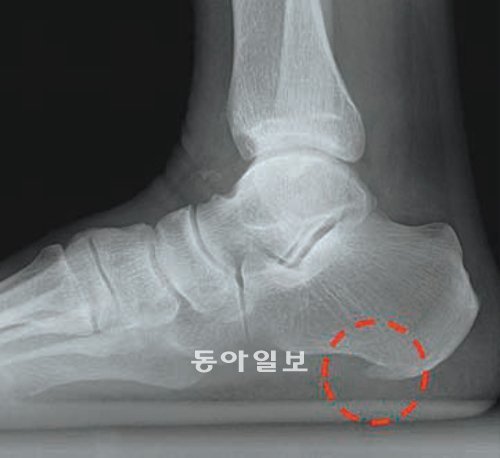

갑자기 무리하게 운동하거나 딱딱한 신발을 신어 발에 스트레스가 쌓이면 ‘발바닥 근막염’이 생긴다. 걷기 힘들 정도로 통증이 심하다. 적절한 체중을 유지하고 과격한 운동을 피하면 막을 수 있다. 서울대병원 제공